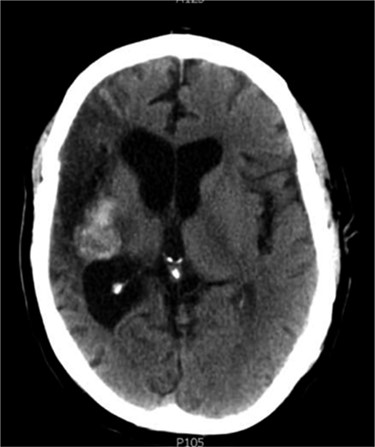

Between 2005 and 2012, the clinical condition remained stable and there were no significant radiological changes identified (Fig. 2). In July 2012, the patient re-presented with worsening left sided weakness and a left sided homonymous hemianopia. CT scan at this time demonstrated a 4 × 4cm well-defined mass of CSF density in addition to the pre-existing lesion in the right external capsule. Neither enhanced with contrast and there was no significant midline shift. An MRI head showed the lesion to contain a significant solid component. It appeared somewhat vascular and there was suspicion that it could represent a low-grade tumour (Fig. 3). The patient underwent a right-sided craniotomy to remove the mass.

Axial MRI head (2012) demonstrating 4 × 4 cm solid mass with surrounding fluid enhancement.

Histological analysis showed large fragments of collagenous tissue. The central parts of the specimen had cholesterol clefts, macrophages and numerous foreign body type multinucleated giant cells. Vessels with calcified walls were also identified. The surrounding capsule contained reactive glial cells and vessels with perivascular inflammation. It was concluded that these findings were consistent with a marked foreign body response to a retained surgical swab.